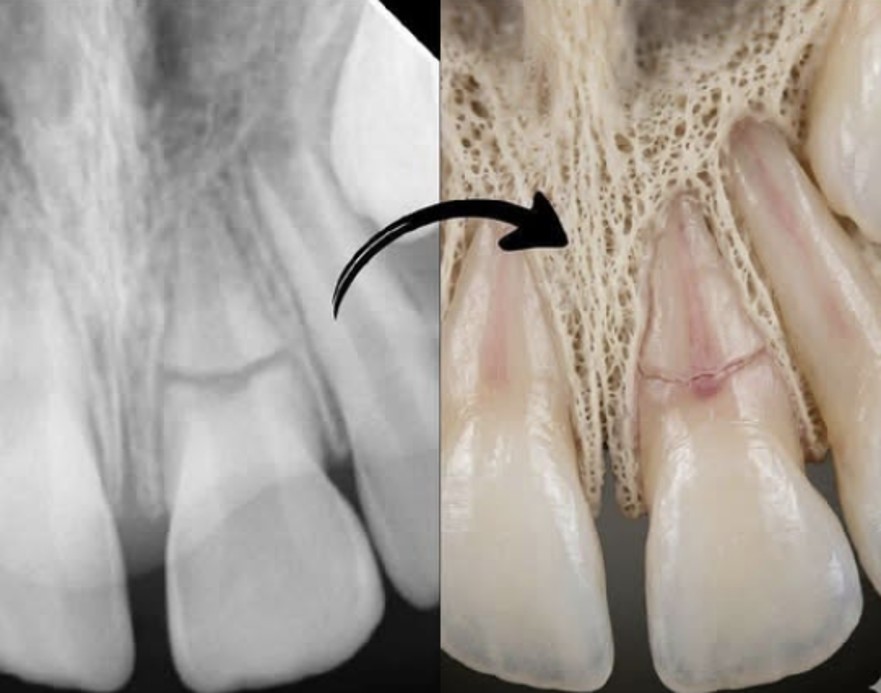

Move beyond 2D radiographs. Learn how to use CBCT to detect proximal, occlusal, and root caries with greater precision, and understand the limitations and benefits of 3D imaging for caries.

Detect periapical pathology, complex root anatomy, and vertical root fractures that are invisible on 2D films. Learn the CBCT criteria that change treatment decisions and improve outcomes.